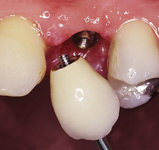

Klasickým příkladem a indikací pro použití implantátu je ztráta jednoho zubu (v tomto případě v předním – frontálním úseku) v jinak zdravém, nepoškozeném chrupu.

Nejčastější příčinou takové ztráty je sportovní nebo dopravní úraz.